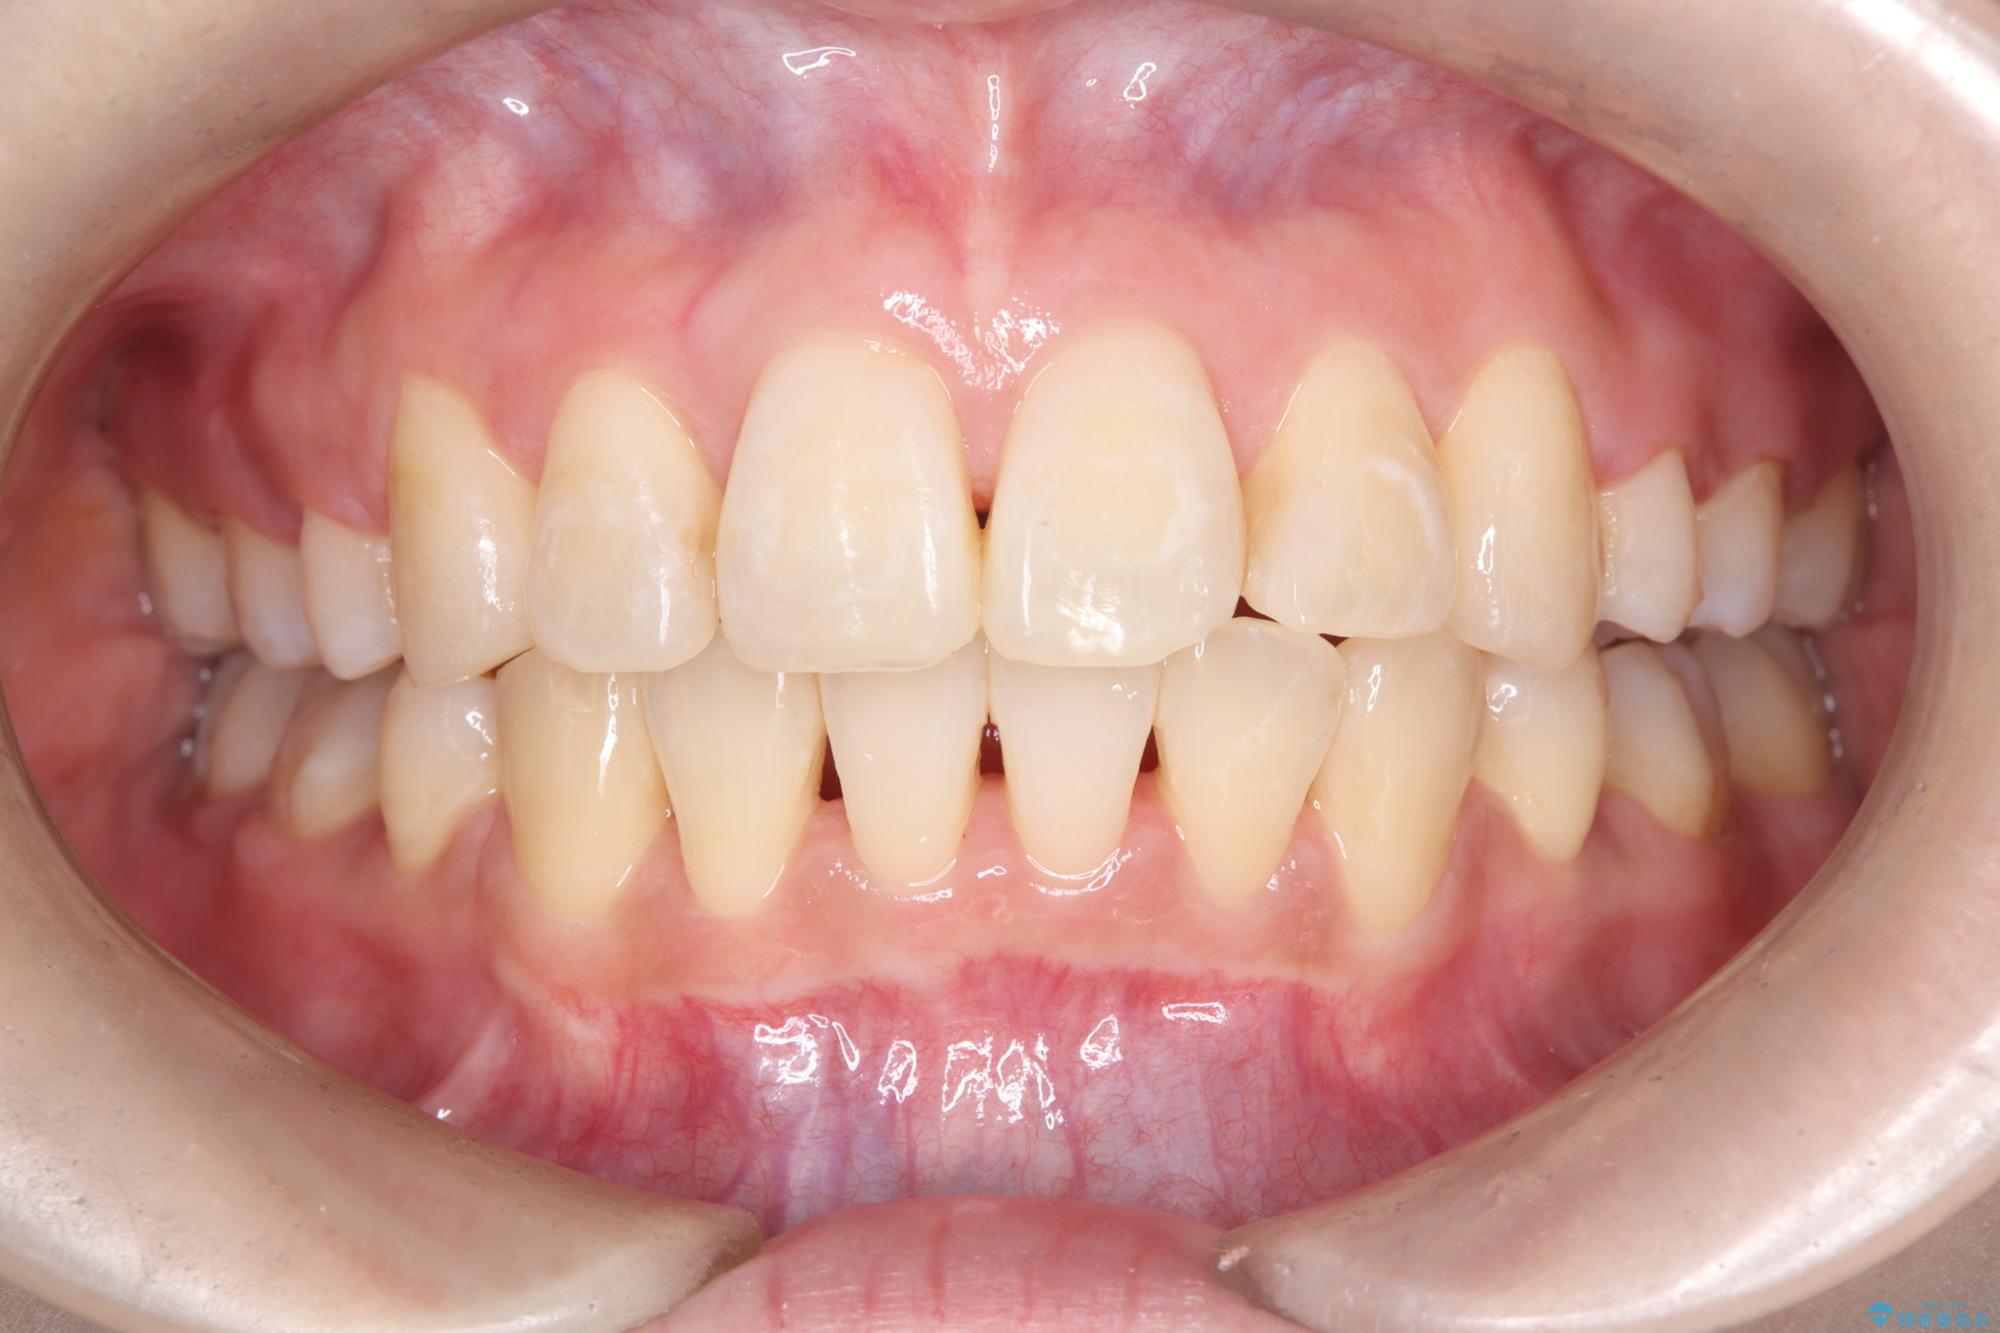

- 八重歯(叢生)と、上下の歯の中心線(正中)がずれていることを主訴にご来院されました。精密な検査の結果、歯列全体のスペースが大幅に不足しており、八重歯を正しい位置に配列し、正中のズレを改善するためには、上下左右の第一小臼歯を抜歯する必要があると診断。装置には、目立ちにくい審美ワイヤーを使用し、見た目を気にせず、機能性と審美性が完璧に整った咬み合わせを目指す治療計画を立案しました。

今回の矯正治療では、まず計画通り上下左右の小臼歯4本を抜歯し、八重歯や正中のズレを解消するための十分なスペースを確保しました。装置には、目立ちにくい白いブラケットとワイヤーを使用した審美ワイヤー矯正を採用。

八重歯: 突出していた八重歯を歯列内に誘導し、デコボコを解消しました。

正中のズレ: 歯を左右対称に移動させることで、上下の歯の中心線を正確に合わせ、顔全体のバランスも改善しました。

治療の結果、長年気にされていた八重歯と正中のズレが解消し、機能的にも整った理想的な歯並びを獲得。目立たない装置で治療を完遂し、自信を持って笑える美しい笑顔を手に入れていただけました。